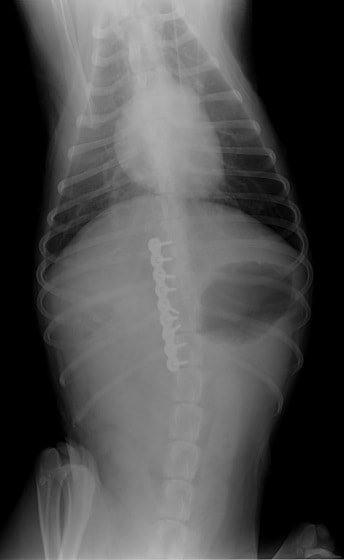

症例:交通事故による椎体脱臼

柴犬:9歳、避妊雌

交通事故直後、胸腰部に激しい疼痛、両後肢に完全麻痺を認め、シェフシェリントン徴候を呈していました。レントゲン検査において、第11-12胸椎間の脱臼が認められました。

脊髄の減圧、脊柱管の再構築・安定化を目的に、片側椎弓切除術およびMatrixMANDIBLE Plateによる椎体固定を実施しました。

隣接椎体を架橋するようにプレートを設置しました。

術後レントゲン写真